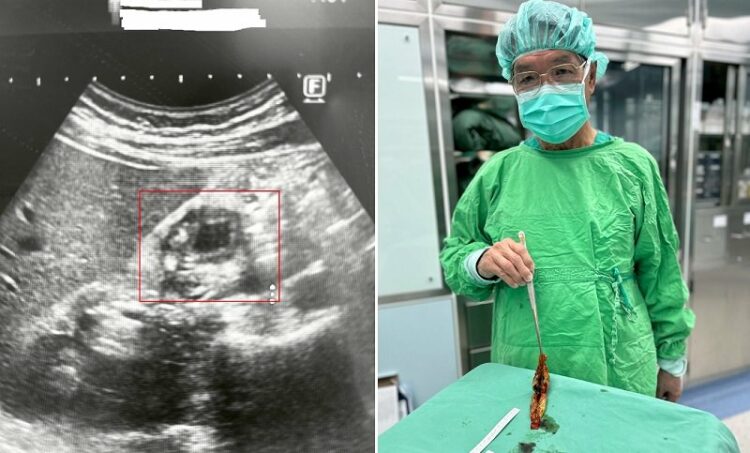

圖左:49歲男子因心窩悶痛與右上腹脹痛,五年來四處求醫,近期至博田國際醫院肝膽胰外科看診並接受檢查時,才被發現罹患「膽囊腺肌症」。圖右/博田國際醫院肝膽胰外科李金德教授以單孔腹腔鏡,進行膽囊切除手術。

49歲的林姓男子五年來,因心窩悶痛與右上腹脹痛四處求醫,做過胃鏡與多次超音波,皆僅顯示輕微胃炎或無結石異常,反覆發作的疼痛成了長期困擾,卻始終找不到病因,近期至博田國際醫院肝膽胰外科看診並接受檢查時,才被發現膽囊壁竟異常廣泛性增厚達正常的六倍,進一步電腦斷層掃描終於確認,是臨床上常與膽結石混淆的「膽囊腺肌症」。

李教授以單孔腹腔鏡為其進行膽囊切除手術,術後林先生迅速恢復,病理證實為膽囊腺肌症且無惡性變化。他多年無法放鬆吃飯、不敢碰油膩食物的生活終於解除,回診時也表示身體狀況大幅改善,感謝醫師協助找出多年來難解的病因。